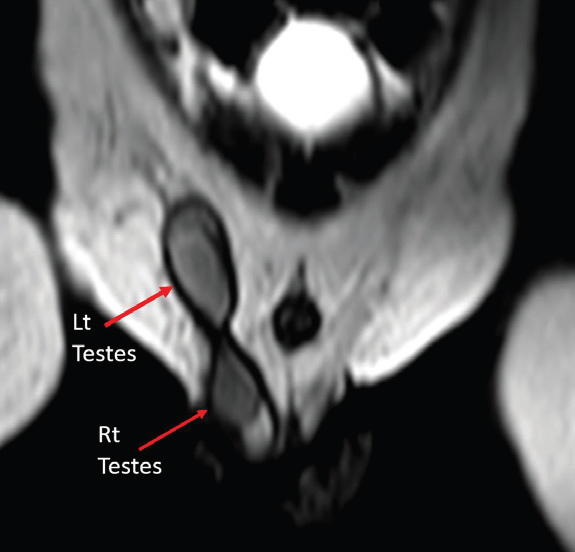

MRI pelvis was performed for soft tissue characterization. T2- weighted sequences demonstrated two testes on the right side—one within the scrotum and the other at the superficial inguinal ring. The ectopic left testis was smaller than the right testis. Additionally, an intermediate-signal-intensity structure was noted in the right inguinal canal, distinct from both testes, suggestive of a Müllerian derivative [Figure 4-6].

Figure 4: Coronal T2-weighted MRI showing bilateral testes located on the

same side of the pelvis—one in the scrotum and the other in the inguinal ring.

Figure 5: Oblique sagittal T2-weighted MRI demonstrating a soft tissue

structure in the superficial inguinal ring, different in signal intensity from the

testes, suspicious for Müllerian remnant.